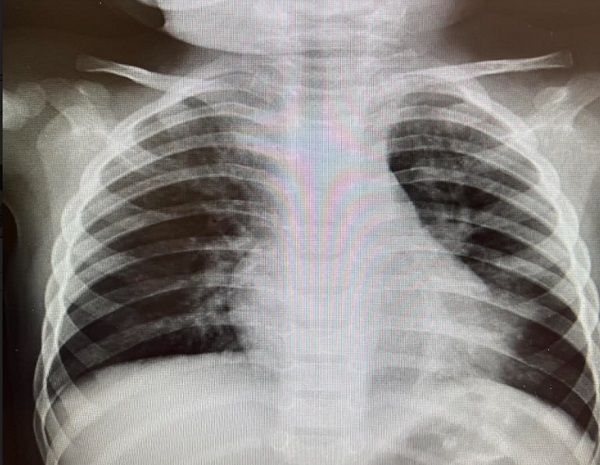

Niño de 25 meses que presenta en marzo del 2023 episodio de bronconeumonía bilateral con ingreso hospitalario por insuficiencia respiratoria (Figura 1).

Figura 1. Bronconeumonía bilateral